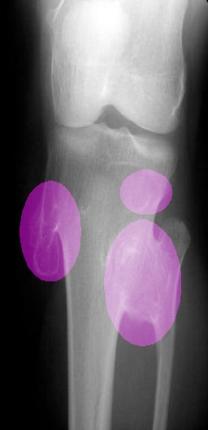

Legs / Knees xrays

The MHE Research Foundation's X-Ray & Image Gallery

These X-rays & Images were obtained from a variety of children with MHE / MO / HME